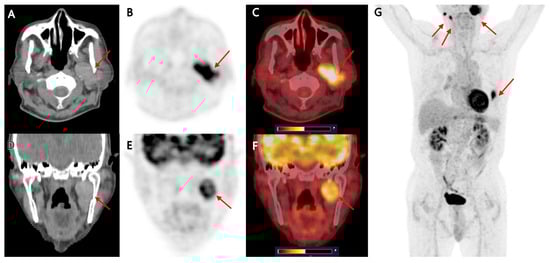

Background: The purpose of this study was to examine the relationship between qualitative characteristics and quantitative parameters from contrast-enhanced ultrasound (CEUS) and microvessel density (MVD) in hepatoblastoma (HB), as well as to investi...